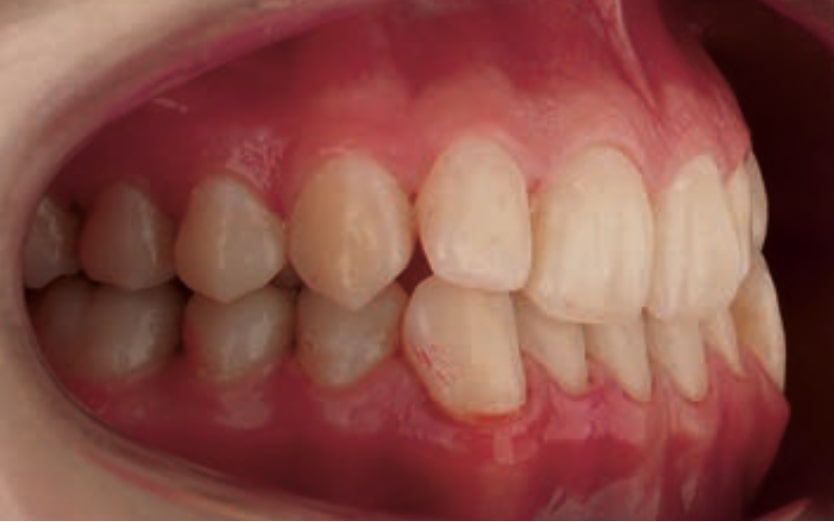

Chief complaint: The patient, a 19-year-old woman, was evaluated to undergo orthodontic treatment using the Angel Aligner Pro system. She presents with a skeletal Class III, mesofacial, with a dental Class III malocclusion and a 2 mm deviation of the lower midline to the left. Teeth 33 and 43 are out of the arch and cortical bone, with a crossbite issue on tooth 33. Fortunately, no functional issues affecting swallowing or breathing have been detected. The patient’s motivation for starting treatment was a general review of her dental and aesthetic health. The soft tissue analysis reveals mandibular protrusion that influences her facial profile. This diagnosis highlights the need for a comprehensive approach to address dental and skeletal misalignments, improving both the patient’s functionality and facial aesthetics.

- Dental Class III, 2 mm deviation of the lower midline to the left. 33 and 43 out of the arch and the cortical bone.

- Crossbite of 33.